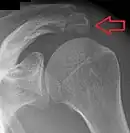

Épaule

Un os acromial se forme lorsque l'un de ses quatre centres d'ossification ne parvient pas à fusionner. Ces quatre centres d'ossification sont appelés de la pointe à la base pré-acromion, méso-acromion, méta-acromion et basi-acromion. Dans la plupart des cas, les trois premiers fusionnent entre 15 et 18 ans, tandis que la partie de base fusionne avec la colonne scapulaire à 12 ans. Un tel échec de fusion se produit dans 1 à 15 % des cas[15],[16]. Cela provoque rarement une douleur.